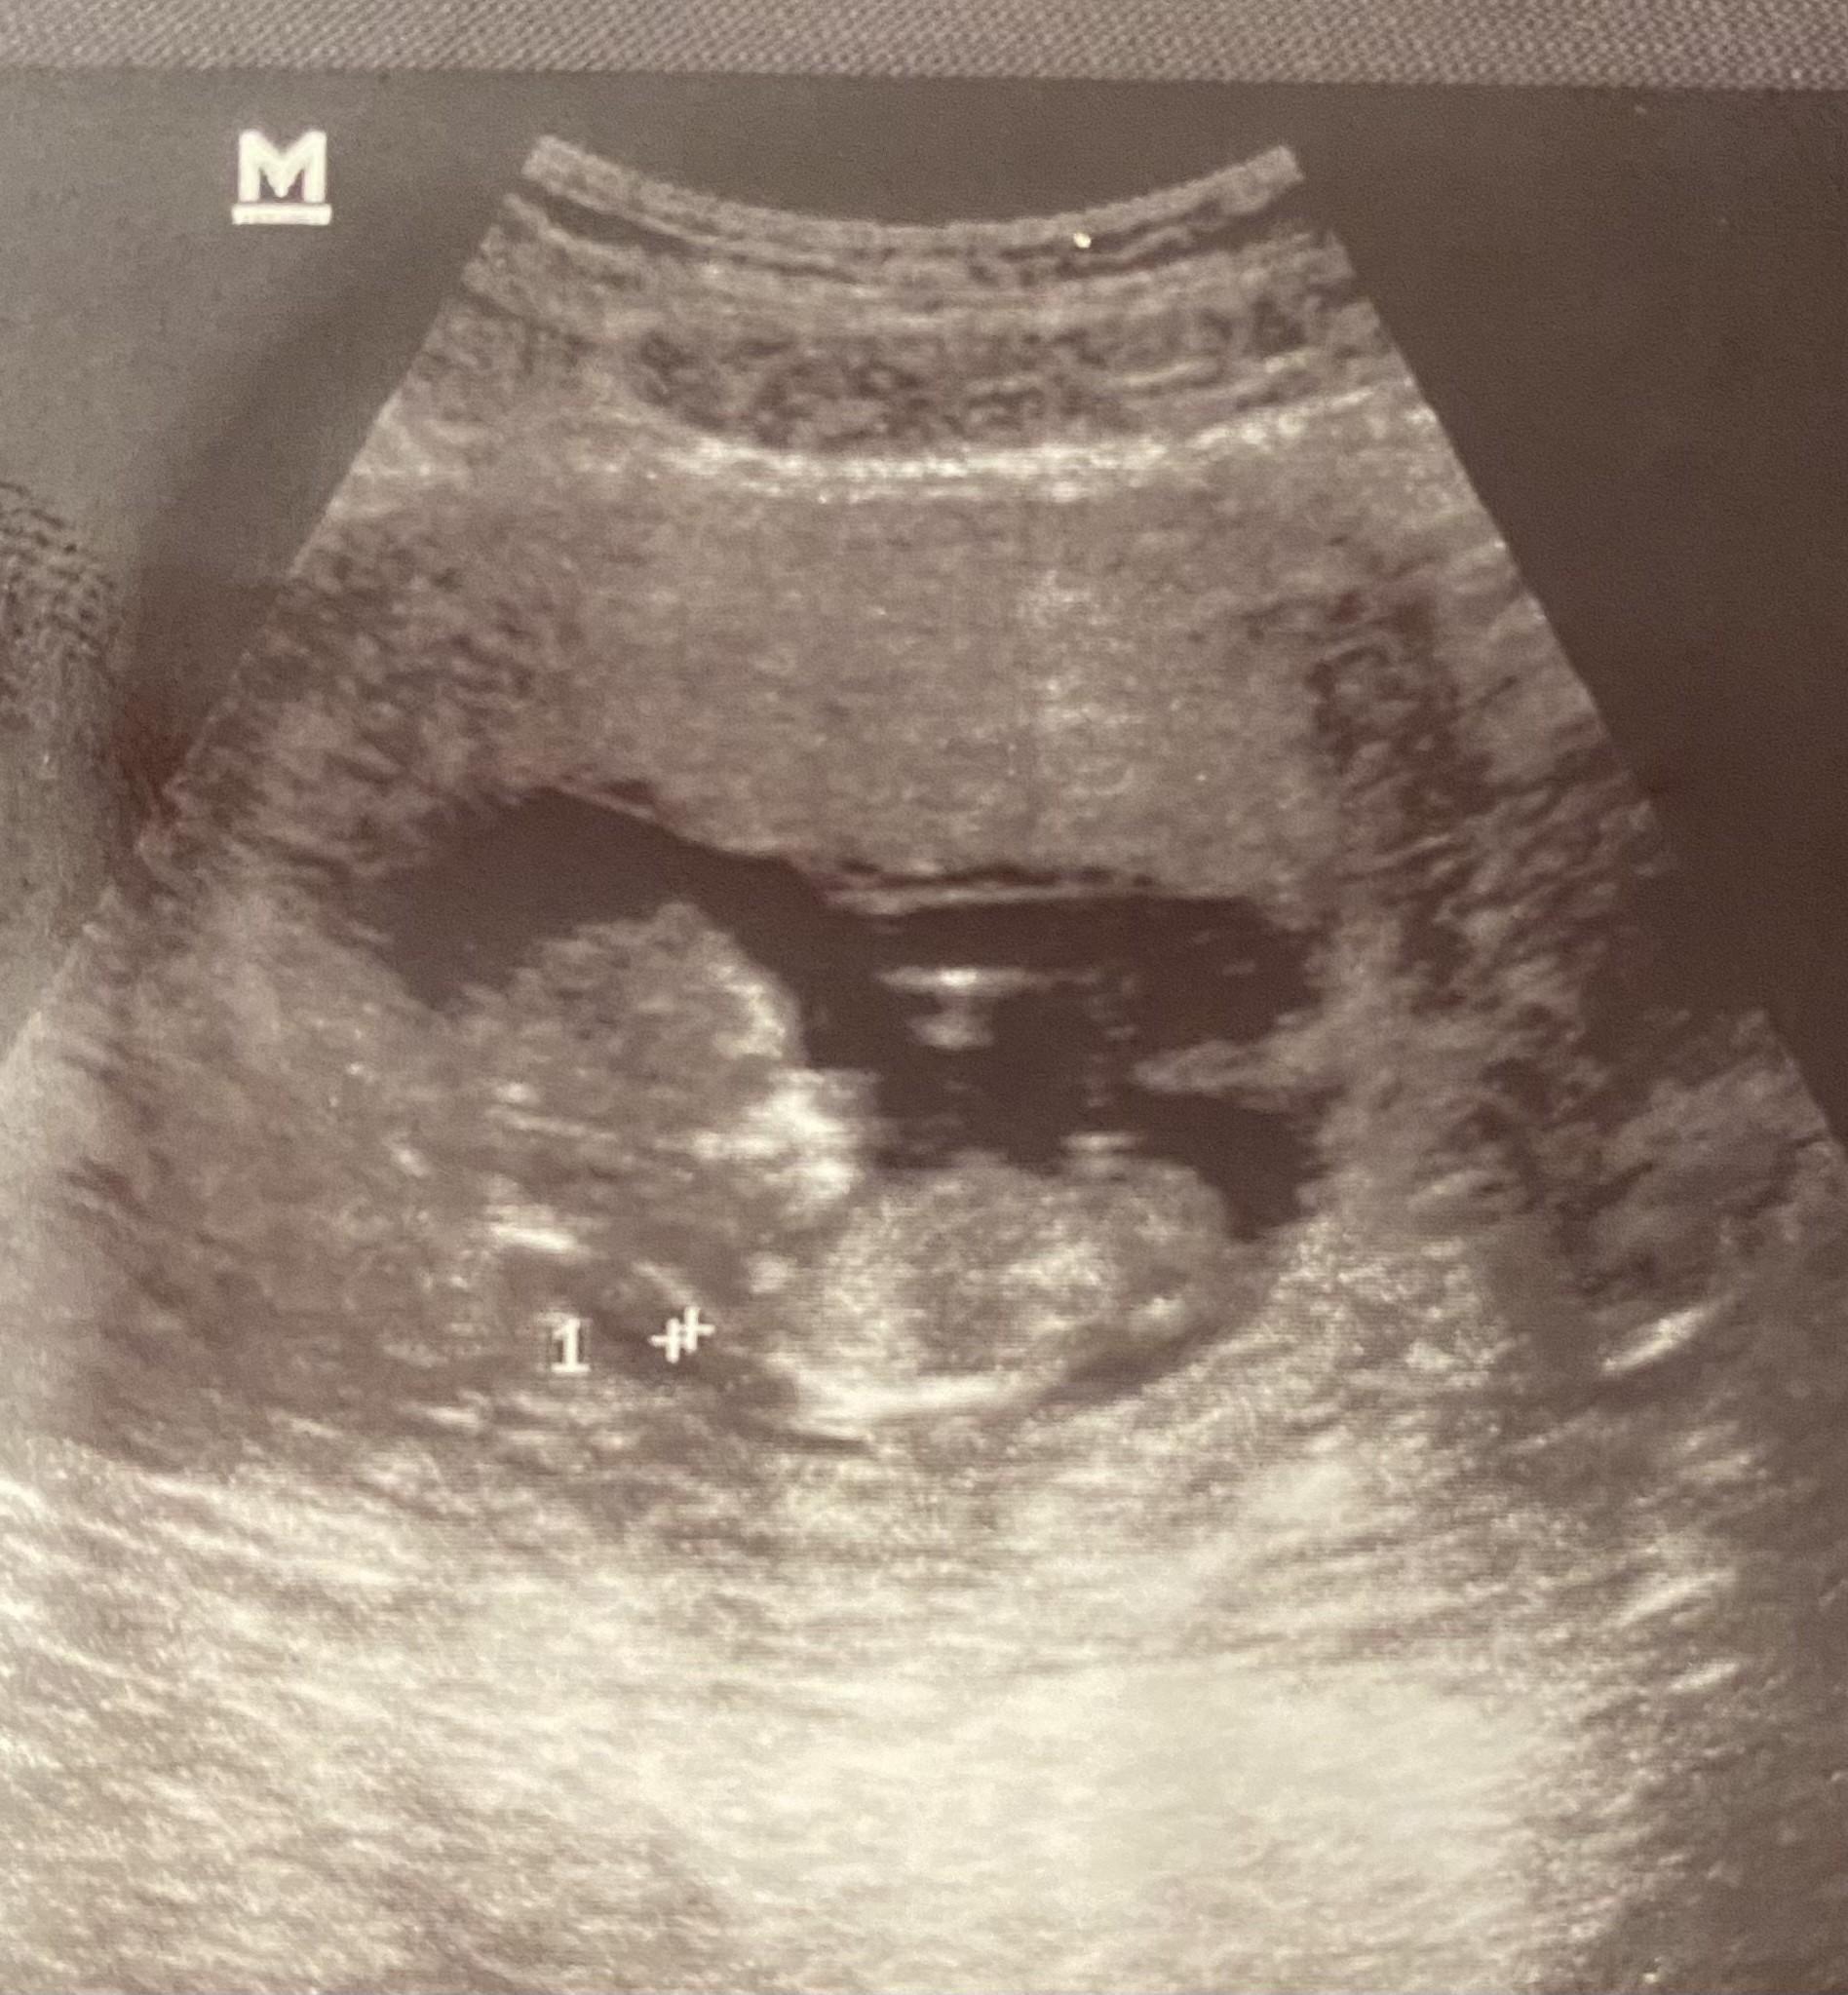

Znalazłam foto syna z 12 tygodnia ❤️ Już buźkę widać . Obyśmy wszystkie dotrwały do tego najgorszego chyba ,12 tygodnia.

Załączniki

• 15D94311-1FB9-4B01-8CA9-1B17C4AE3609.jpeg

15D94311-1FB9-4B01-8CA9-1B17C4AE3609.jpeg

701,4 KB · Wyświetleń: 109